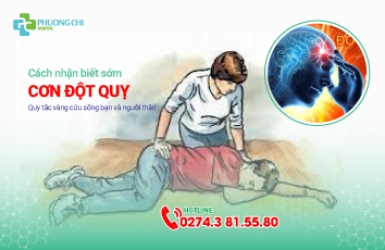

Cách nhận biết sớm cơn đột quỵ

Tổ chức Đột quỵ của Thế giới ước tính, cứ mỗi 6 người sẽ có 1 người bị đột quỵ. Theo đó, chỉ riêng tại Việt Nam, mỗi năm có hơn 200.000 người bị đột quỵ. Việc phát hiện sớm những dấu hiệu của chứng bệnh này là điều rất quan trọng để có thể giảm thiểu những hậu quả nguy hiểm của bệnh và rút ngắn thời gian điều trị.